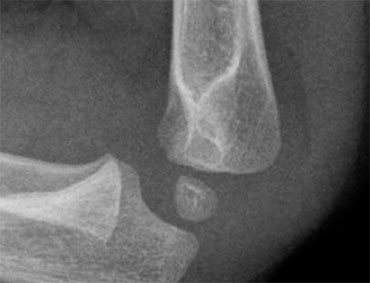

The diagnosis of a lateral condyle fracture can be challenging.

Fracture lines are sometimes barely visible (figure).

Remembering the fact that the lateral condyle fracture is the second most common elbow-fracture in children and because you know where to look for will help you

Lateral condyle fracture. On the x-ray only a small metaphyseal fragment is visible. The detatched fragment however is larger than it appears on the radiograph. The fracture extents into the lateral ridge of the trochlea. Elbow is probably unstable. Lateral condyle fracture. On the x-ray only a small metaphyseal fragment is visible. The detatched fragment however is larger than it appears on the radiograph. The fracture extents into the lateral ridge of the trochlea. Elbow is probably unstable.

Lateral Condyle fractures (4) .

Since most of the structures involved are cartilageneous, it is very difficult to know the exact extent of the fracture.

Lateral Condyle fractures (5)

In lateral condyle fractures the actual fracture line can be very subtle since the metaphyseal flake of bone may be minor.

The fracture fragment is often rotated.

An oblique view can be helpfull, but usually these are not routinely performed (figure).